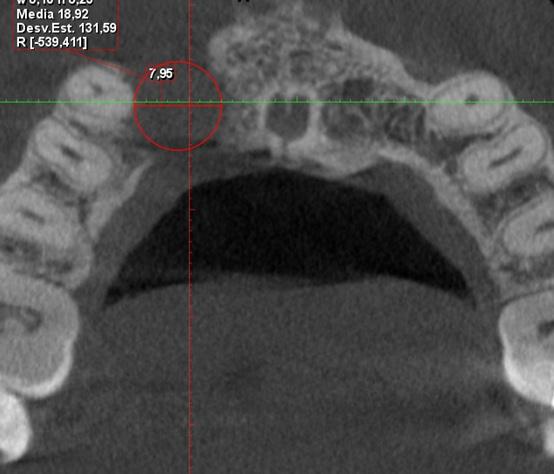

Issuu converts static files into: digital portfolios, online yearbooks, online catalogs, digital photo albums and more. Sign up and create your flipbook.